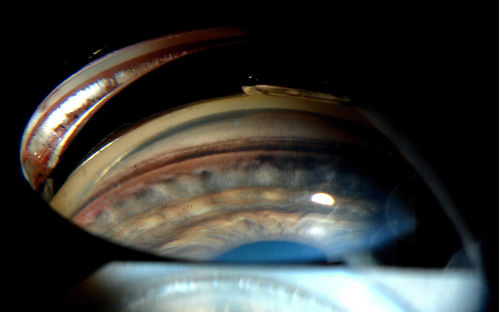

Gonioscopy- Pigmentary Glaucoma Suspect

Patient with no family history of glaucoma, comes in with elevated IOP. During Gonioscopy exam. brown pigment overlying the trabecular meshwork. Also, trans-illumination defects on the iris.